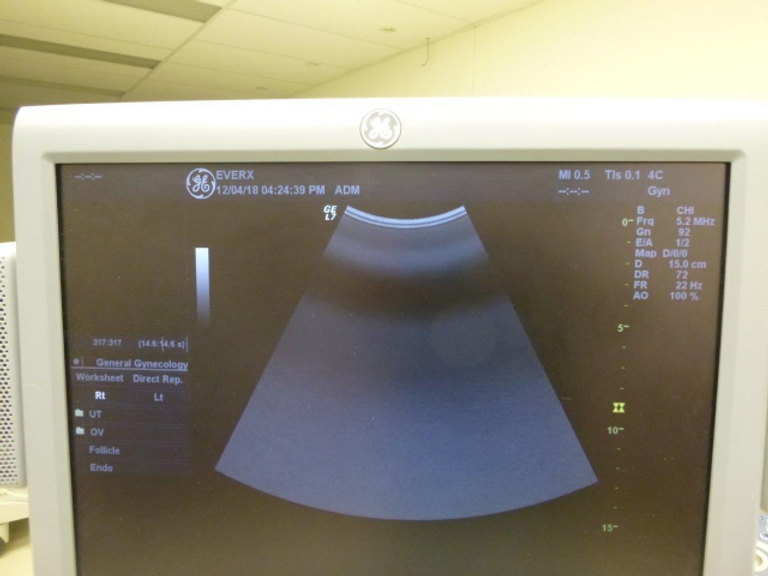

- Advanced Imaging Capabilities: Experience unparalleled image clarity and precision with the Logiq 7’s 3D technology and a comprehensive suite of imaging features, including Power Doppler Imaging, M-Mode, and Color Flow Mode (CFM).

- Wide Range of Clinical Applications: From abdominal and OB/GYN to small parts, pediatric, vascular, and cardiac diagnostic testing, the Logiq 7 supports a full spectrum of clinical applications, making it a versatile solution for diverse healthcare settings.